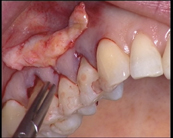

3. 14 h 19 : Pénétration pour tunnélisation en épaisseur totale en préservant les papilles par décollement vertical, toujours en contact avec l’os.

Sofia Aroca aborde le site opératoire directement avec un instrument de tunnélisation à partir des faces vestibulaires, en respectant les papilles. Elle commente elle-même son geste.

« J’effectue un décollement vertical en épaisseur totale. Je veille à préserver les papilles. »

Le geste est lent mais précis, l’avancée très progressive.

« Les tissus sont très fi ns, mais heureusement bien adhérents car ils sont sains. Dans ce genre de récessions, des balcons osseux se forment. La nécessité de rester au contact osseux pour être sûr de décoller en épaisseur totale rend cette étape délicate. »